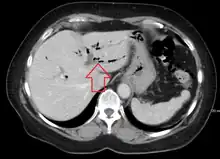

| CT scan of pneumobilia |

Pneumobilia is the presence of gas in the biliary system. It is typically detected by ultrasound or a radiographic imaging exam, such as CT, or MRI. It is a common finding in patients that have recently undergone biliary surgery or endoscopic biliary procedure. While the presence of air within biliary system is not harmful, this finding may alternatively suggest a pathological process, such as a biliary-enteric anastomosis, an infection of the biliary system, an incompetent sphincter of Oddi, or spontaneous biliary-enteric fistula.